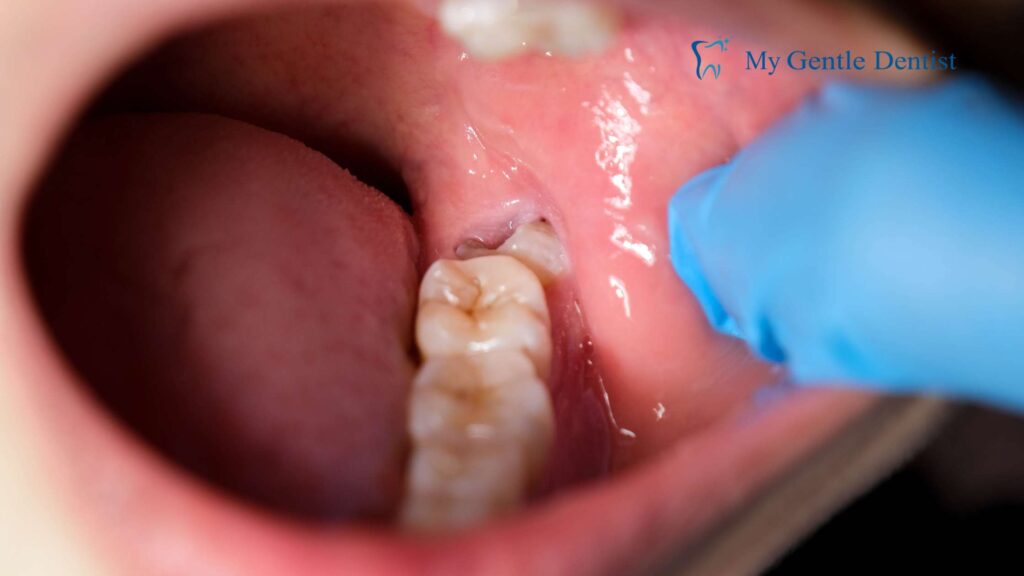

- Impacted Teeth: If a wisdom tooth cannot fully emerge, it may become impacted. Impacted wisdom teeth can grow at odd angles or sideways, causing continuous pressure and discomfort in the jaw.

- Gum Infection: Partially erupted wisdom teeth create a gap where food and bacteria can become trapped, leading to an infection called pericoronitis that results in swelling, pain, and sometimes pus.